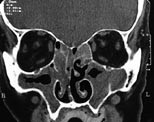

Pasienten . En 67 år gammel mann med kjent atopisk disposisjon og behandlingskrevende astma bronchiale ble henvist til Øre-nese-halsavdelingen, Nordland Sentralsykehus, etter mangeårige plager med nasalstenose. Pasienten var usikker på om han hadde fått fjernet nasale polypper tidligere. Han hadde også i perioder vært plaget med rhinoré og man mistenkte en allergisk rhinitt. Koronale CT-bilder tatt i juli 1999 viste pansinusitt og nasal polypose (fig 1).